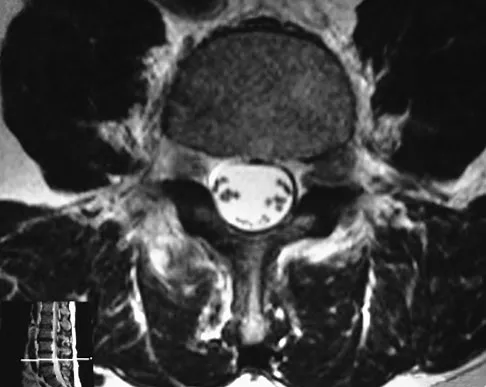

Figure 33 shows the MRI scan of a 55-year-old woman who has had a 6-week history of back and leg pain. Which of the following clinical scenarios is most consistent with the MRI scan findings at L4-L5?

Detailed Explanation